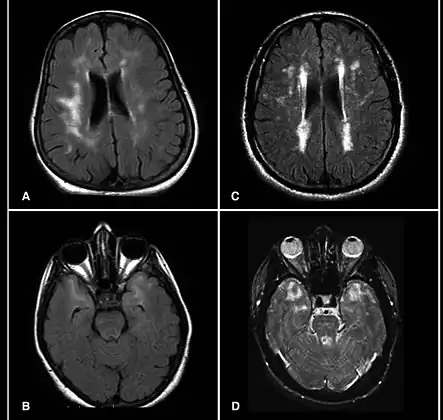

MRI scans showing hyperintensities

A hyperintensity or T2 hyperintensity is an area of high intensity on types of magnetic resonance imaging (MRI) scans of the brain of a human or of another mammal that reflect lesions produced largely by demyelination and axonal loss. These small regions of high intensity are observed on T2 weighted MRI images (typically created using 3D FLAIR) within cerebral white matter (white matter lesions, white matter hyperintensities or WMH)[1][2] or subcortical gray matter (gray matter hyperintensities or GMH). The volume and frequency is strongly associated with increasing age.[2] They are also seen in a number of neurological disorders and psychiatric illnesses. For example, deep white matter hyperintensities are 2.5 to 3 times more likely to occur in bipolar disorder and major depressive disorder than control subjects.[3][4] WMH volume, calculated as a potential diagnostic measure, has been shown to correlate to certain cognitive factors.[5] Hyperintensities appear as "bright signals" (bright areas) on an MRI image and the term "bright signal" is occasionally used as a synonym for a hyperintensity.

Hyperintensities are commonly divided into 3 types depending on the region of the brain where they are found. Deep white matter hyperintensities occur deep within white matter, periventricular white matter hyperintensities occur adjacent to the lateral ventricles and subcortical hyperintensities occur in the basal ganglia.